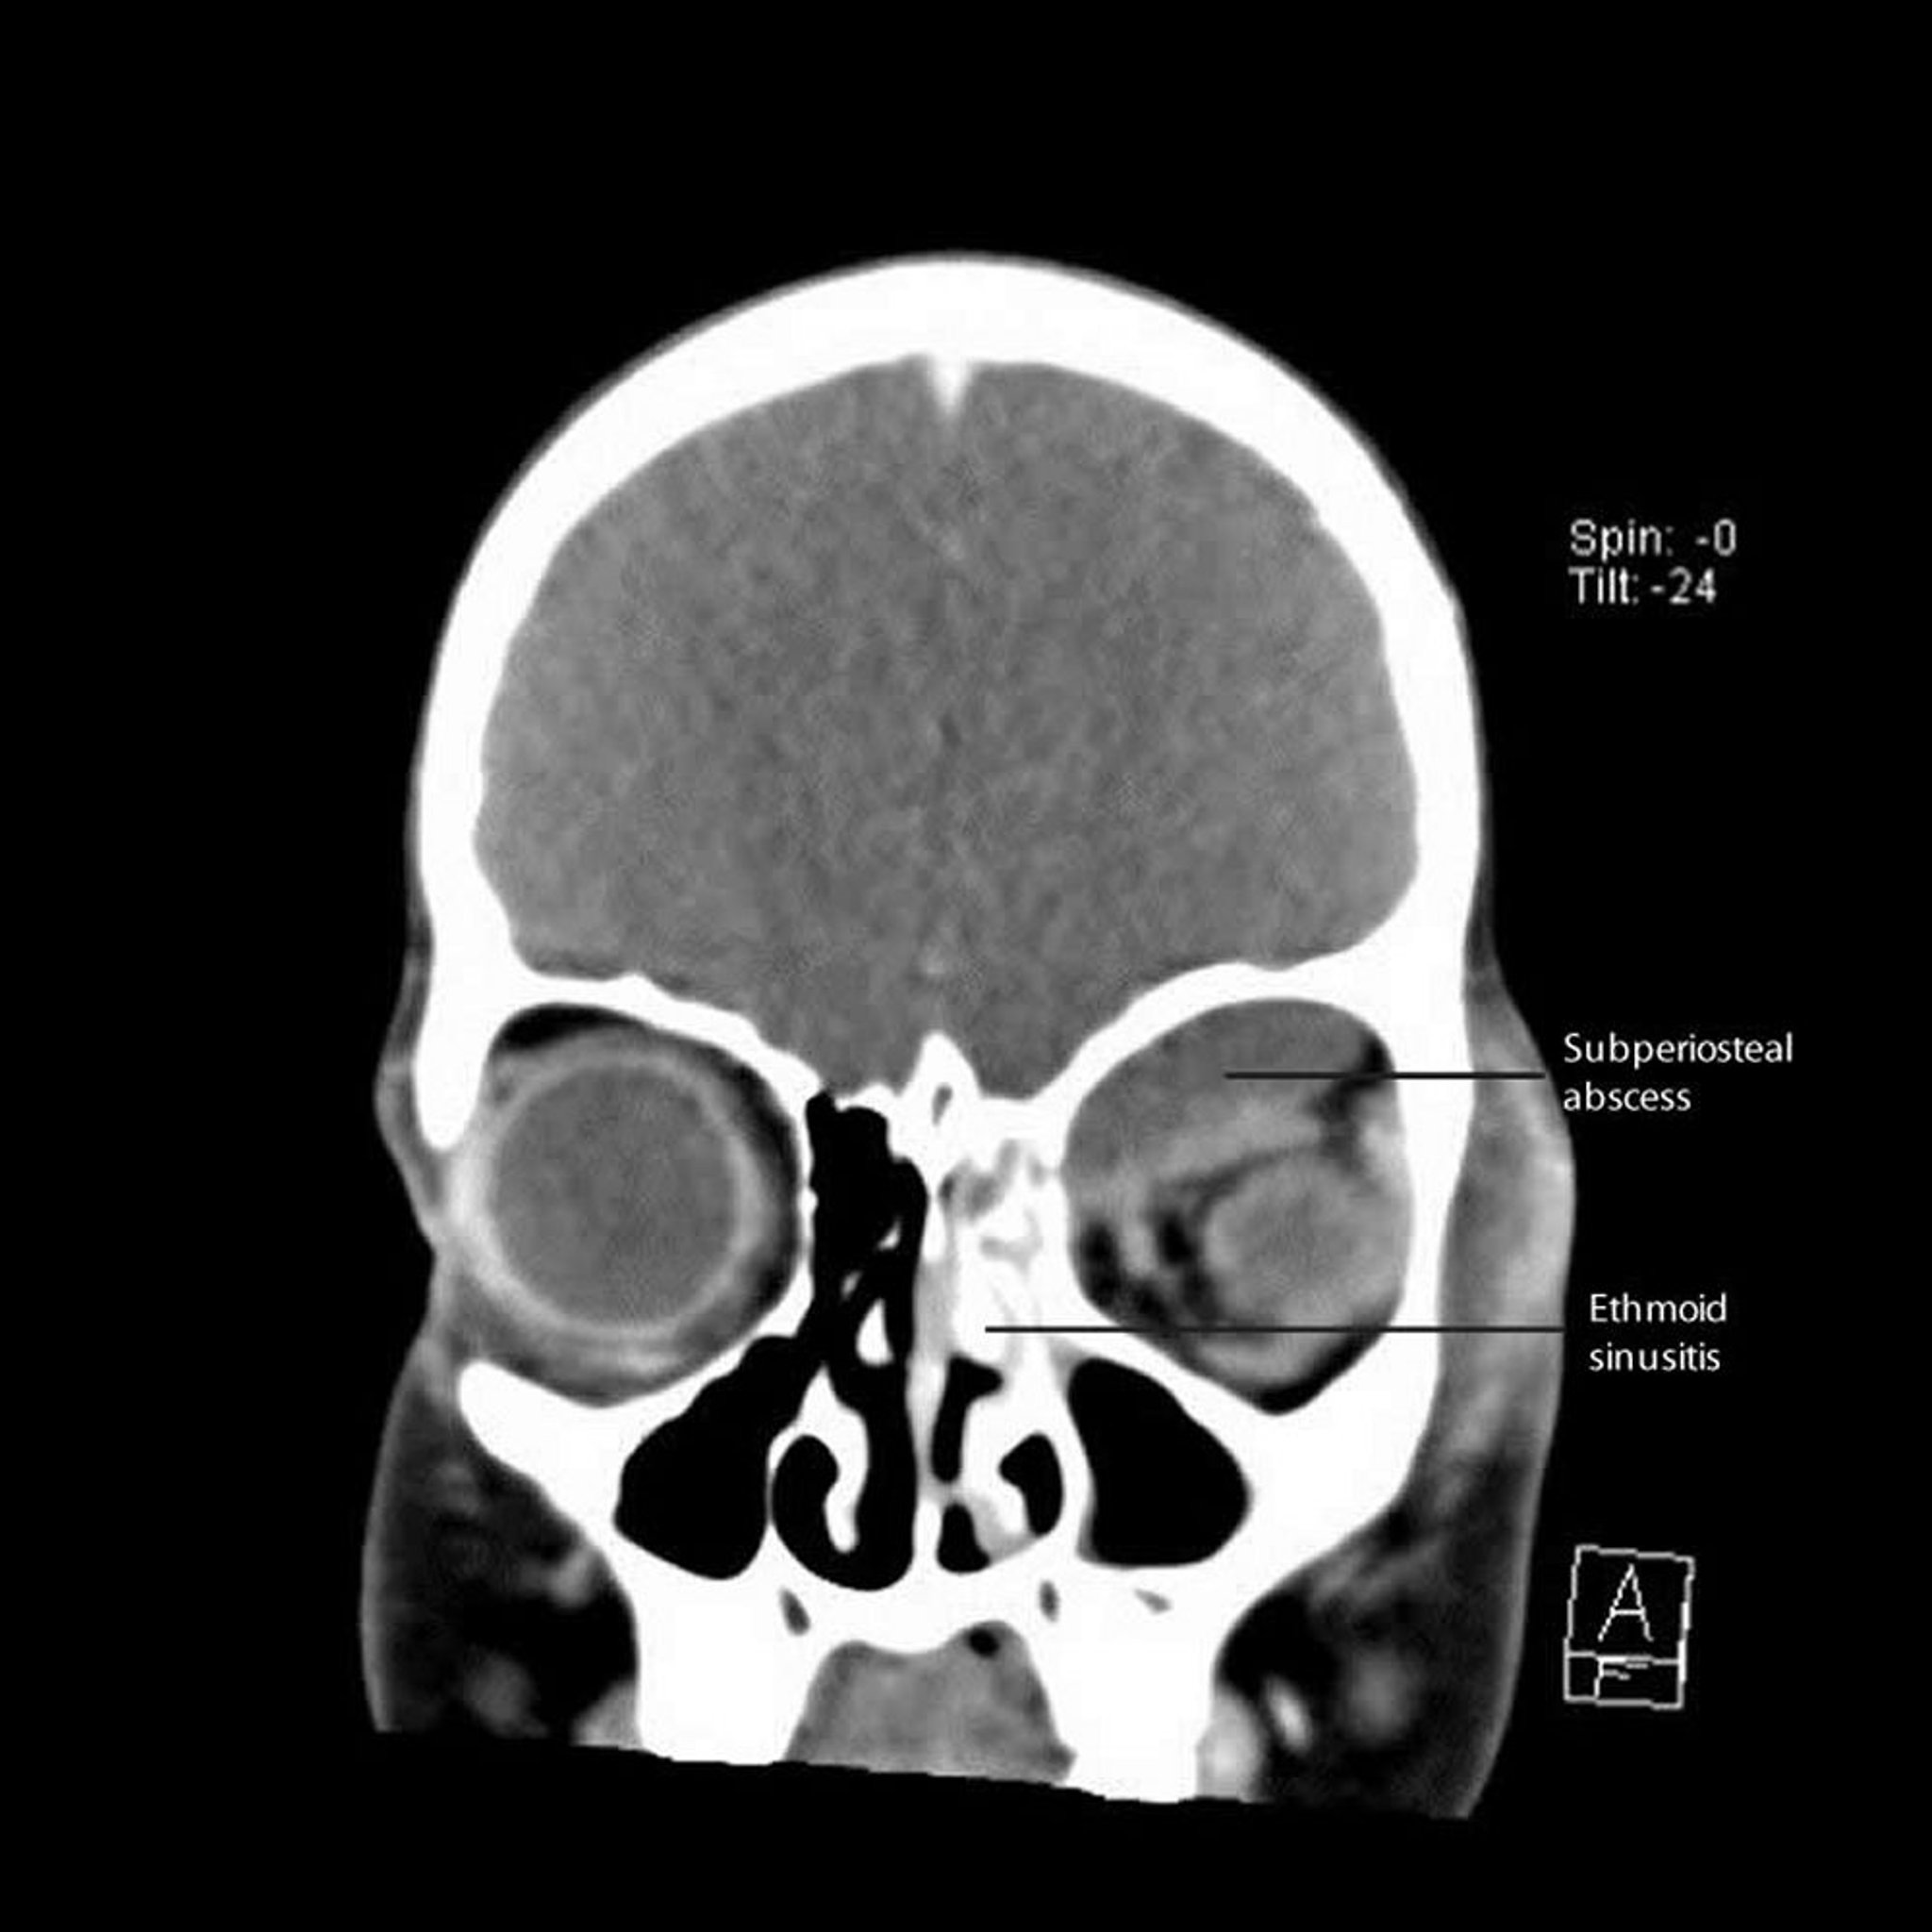

На этом снимке компьютерной томографии показан левосторонний этмоидит с прилегающим субпериостальным абсцессом вдоль медиальной и верхней стенок орбиты.

CT courtesy of James Garrity, MD.